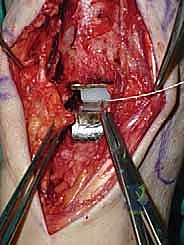

يقوم الدكتور هطيف بعمل شق طولي دقيق في الجزء الأمامي من الكاحل، طوله حوالي 10-15 سم. يتم تشريح الأنسجة بعناية فائقة للوصول إلى المفصل.

* الحماية العصبية الوعائية: هذه هي الخطوة الأكثر حرجاً. يتم تحديد الحزمة الوعائية العصبية (الشريان الظنبوبي الأمامي والعصب الشظوي العميق) وسحبها برفق شديد لحمايتها من أي ضرر جراحي.